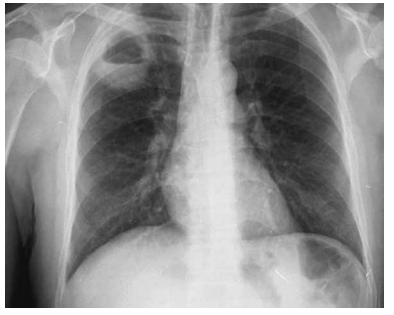

Homem, 49 anos, alcoolista e desnutrido, apresenta quadro de febre diária e expectoração purulenta abundante há 3 semanas. Refere que, associado ao quadro clínico, também está inapetente. Exame físico: regular estado geral, eupneico em ar ambiente. O exame do aparelho respiratório revela a presença de macicez à percussão do ápice pulmonar D, além de redução do murmúrio vesicular nessa topografia. A radiografia de tórax está ilustrada a seguir.

Em relação ao caso exposto, assinale a alternativa correta.